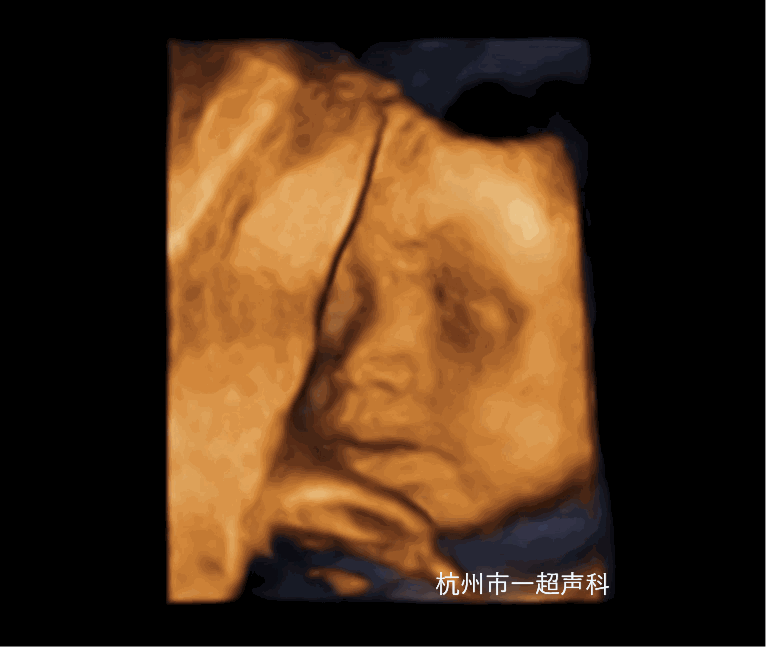

产前超声诊断

我院在2009年开展超声产前诊断,为成人抖音 第一家取得产前诊断资质的医疗机构,技术实力雄厚,超声产前诊断学组目前有主任医师2名,副主任医师3名,高级职称占62.5%,并在市内较早开展了胎儿超声心动图、早中孕期胎儿筛查,超声引导下羊水、绒毛、脐血穿刺、选择性减胎术、宫内输血术等。